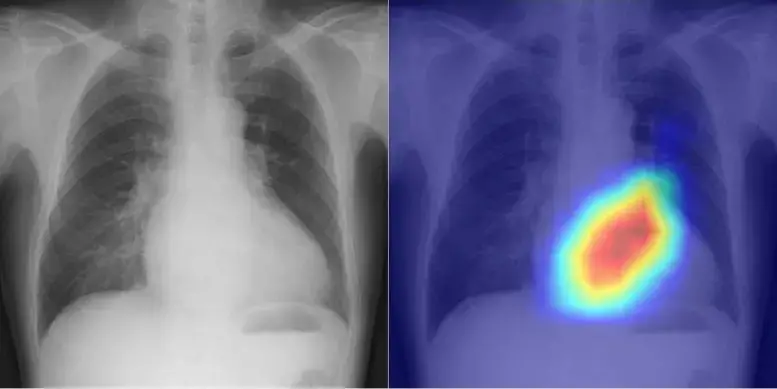

Esquerda: Radiografia de tórax Direita: Visualização dos fundamentos do julgamento da IA. Crédito: Daiju Ueda, OMU.

A equipe do Dr. Ueda desenvolveu com sucesso um modelo que utiliza IA para classificar com precisão as funções cardíacas e doenças cardíacas valvares a partir de radiografias de tórax. Como a IA treinada em um único conjunto de dados enfrenta viés potencial, levando a baixa precisão, a equipe buscou dados multi-institucionais. Assim, foram coletadas 22.551 radiografias de tórax associadas a 22.551 ecocardiogramas de 16.946 pacientes em quatro serviços entre 2013 e 2021. Com as radiografias de tórax definidas como dados de entrada e os ecocardiogramas definidos como dados de saída, o modelo de IA foi treinado para aprender características conectando ambos os conjuntos de dados.

O modelo de IA foi capaz de categorizar precisamente seis tipos selecionados de valvopatias, com a Área sob a Curva, ou AUC, variando de 0,83 a 0,92. (AUC é um índice de classificação que indica a capacidade de um modelo de IA e usa um intervalo de valores de 0 a 1, com quanto mais próximo de 1, melhor.) A AUC foi de 0,92 em um ponto de corte de 40% para detectar a fração de ejeção do ventrículo esquerdo, uma medida importante para monitorar a função cardíaca.